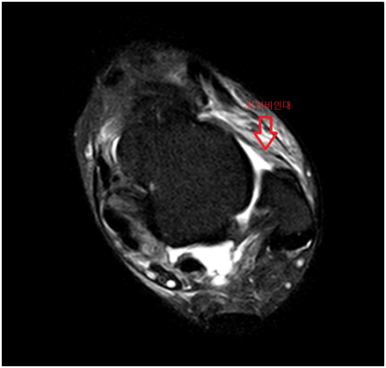

발목 MRI에서 바깥쪽 인대를 구성하는 전거비인대, 후거비인대에 심한 손상, 안쪽 인대를 구성하는 삼각인대 손상, 발목 경비인대결합 손상으로 수술이 가능한 정형외과 병원으로 전원하였습니다.

• MRI 검사: 인대 손상 MRI 검사: 인대 손상